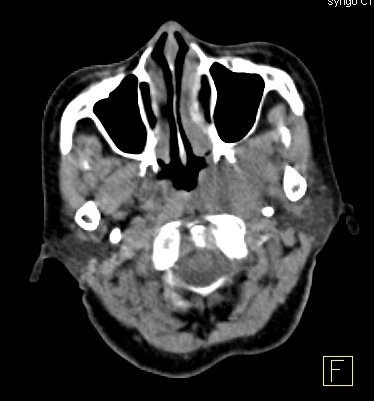

Hình 1 mô tả kết quả ghi hình PET/CT của bệnh nhân Nguyễn Th. B., nữ, 52 tuổi. Gần đây thấy xuất hiện hạch cổ hai bên. Bệnh nhân đi khám và được nội soi vòm mũi họng thì không phát hiện thấy bất thường. X-quang, siêu âm đều cho hình ảnh bình thường. Sinh thiết hạch cổ có kết quả mô bệnh học là ung thư biểu mô không biệt hóa di căn hạch. Vì vậy bệnh nhân được chỉ định chụp PET/CT để phát hiện ung thư nguyên phát. Kết quả chụp PET/CT chỉ thấy hình ảnh ung thư vòm trái, di căn hạch cổ hai bên (tổn thương u vòm nằm dưới niêm mạc thành vòm trái nên không phát hiện được khi nội soi vòm).

Hình 1: Hình ảnh tổn thương nằm dưới niêm mạc thành vòm trái tăng hấp thu FDG mạnh (mũi tên đỏ). Nhiều hạch cổ hai bên tăng hấp thu FDG (mũi tên vàng). Kết luận: Hình ảnh ung thư vòm di căn hạch cổ hai bên.